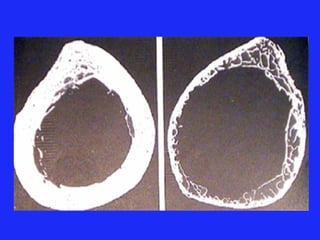

L’OSTEOPOROSE Maladie diffuse du squelette caractérisée par une diminution de la masse osseuse et une altération micro-architecturale du tissu osseux ayant pour conséquence une augmentation du risque fracturaire

L’OSTEOPOROSE Maladie diffusedu squelette caractérisée par une diminution de la masse osseuse et une altération micro-architecturale du tissu osseux ayant pour conséquence une augmentation du risque fracturaire